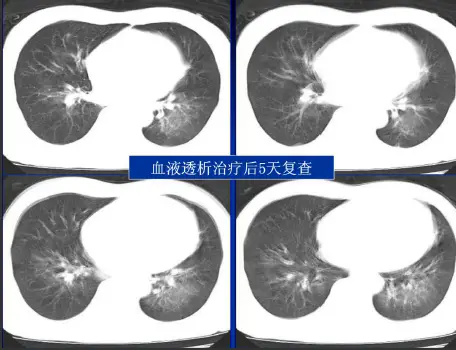

病例:男,33岁,急性肾衰肺水肿。CT表现:①肺间质性肺水肿:两肺血管束增多、增粗,边缘模糊;②肺泡性肺水肿:两肺透光度减低,并见广泛性分布结节样、斑片样密度增高影及毛玻璃样影,边缘模糊,以两肺内、中带分布较明显,形成典型“蝶翼征”;③胸腔积液。